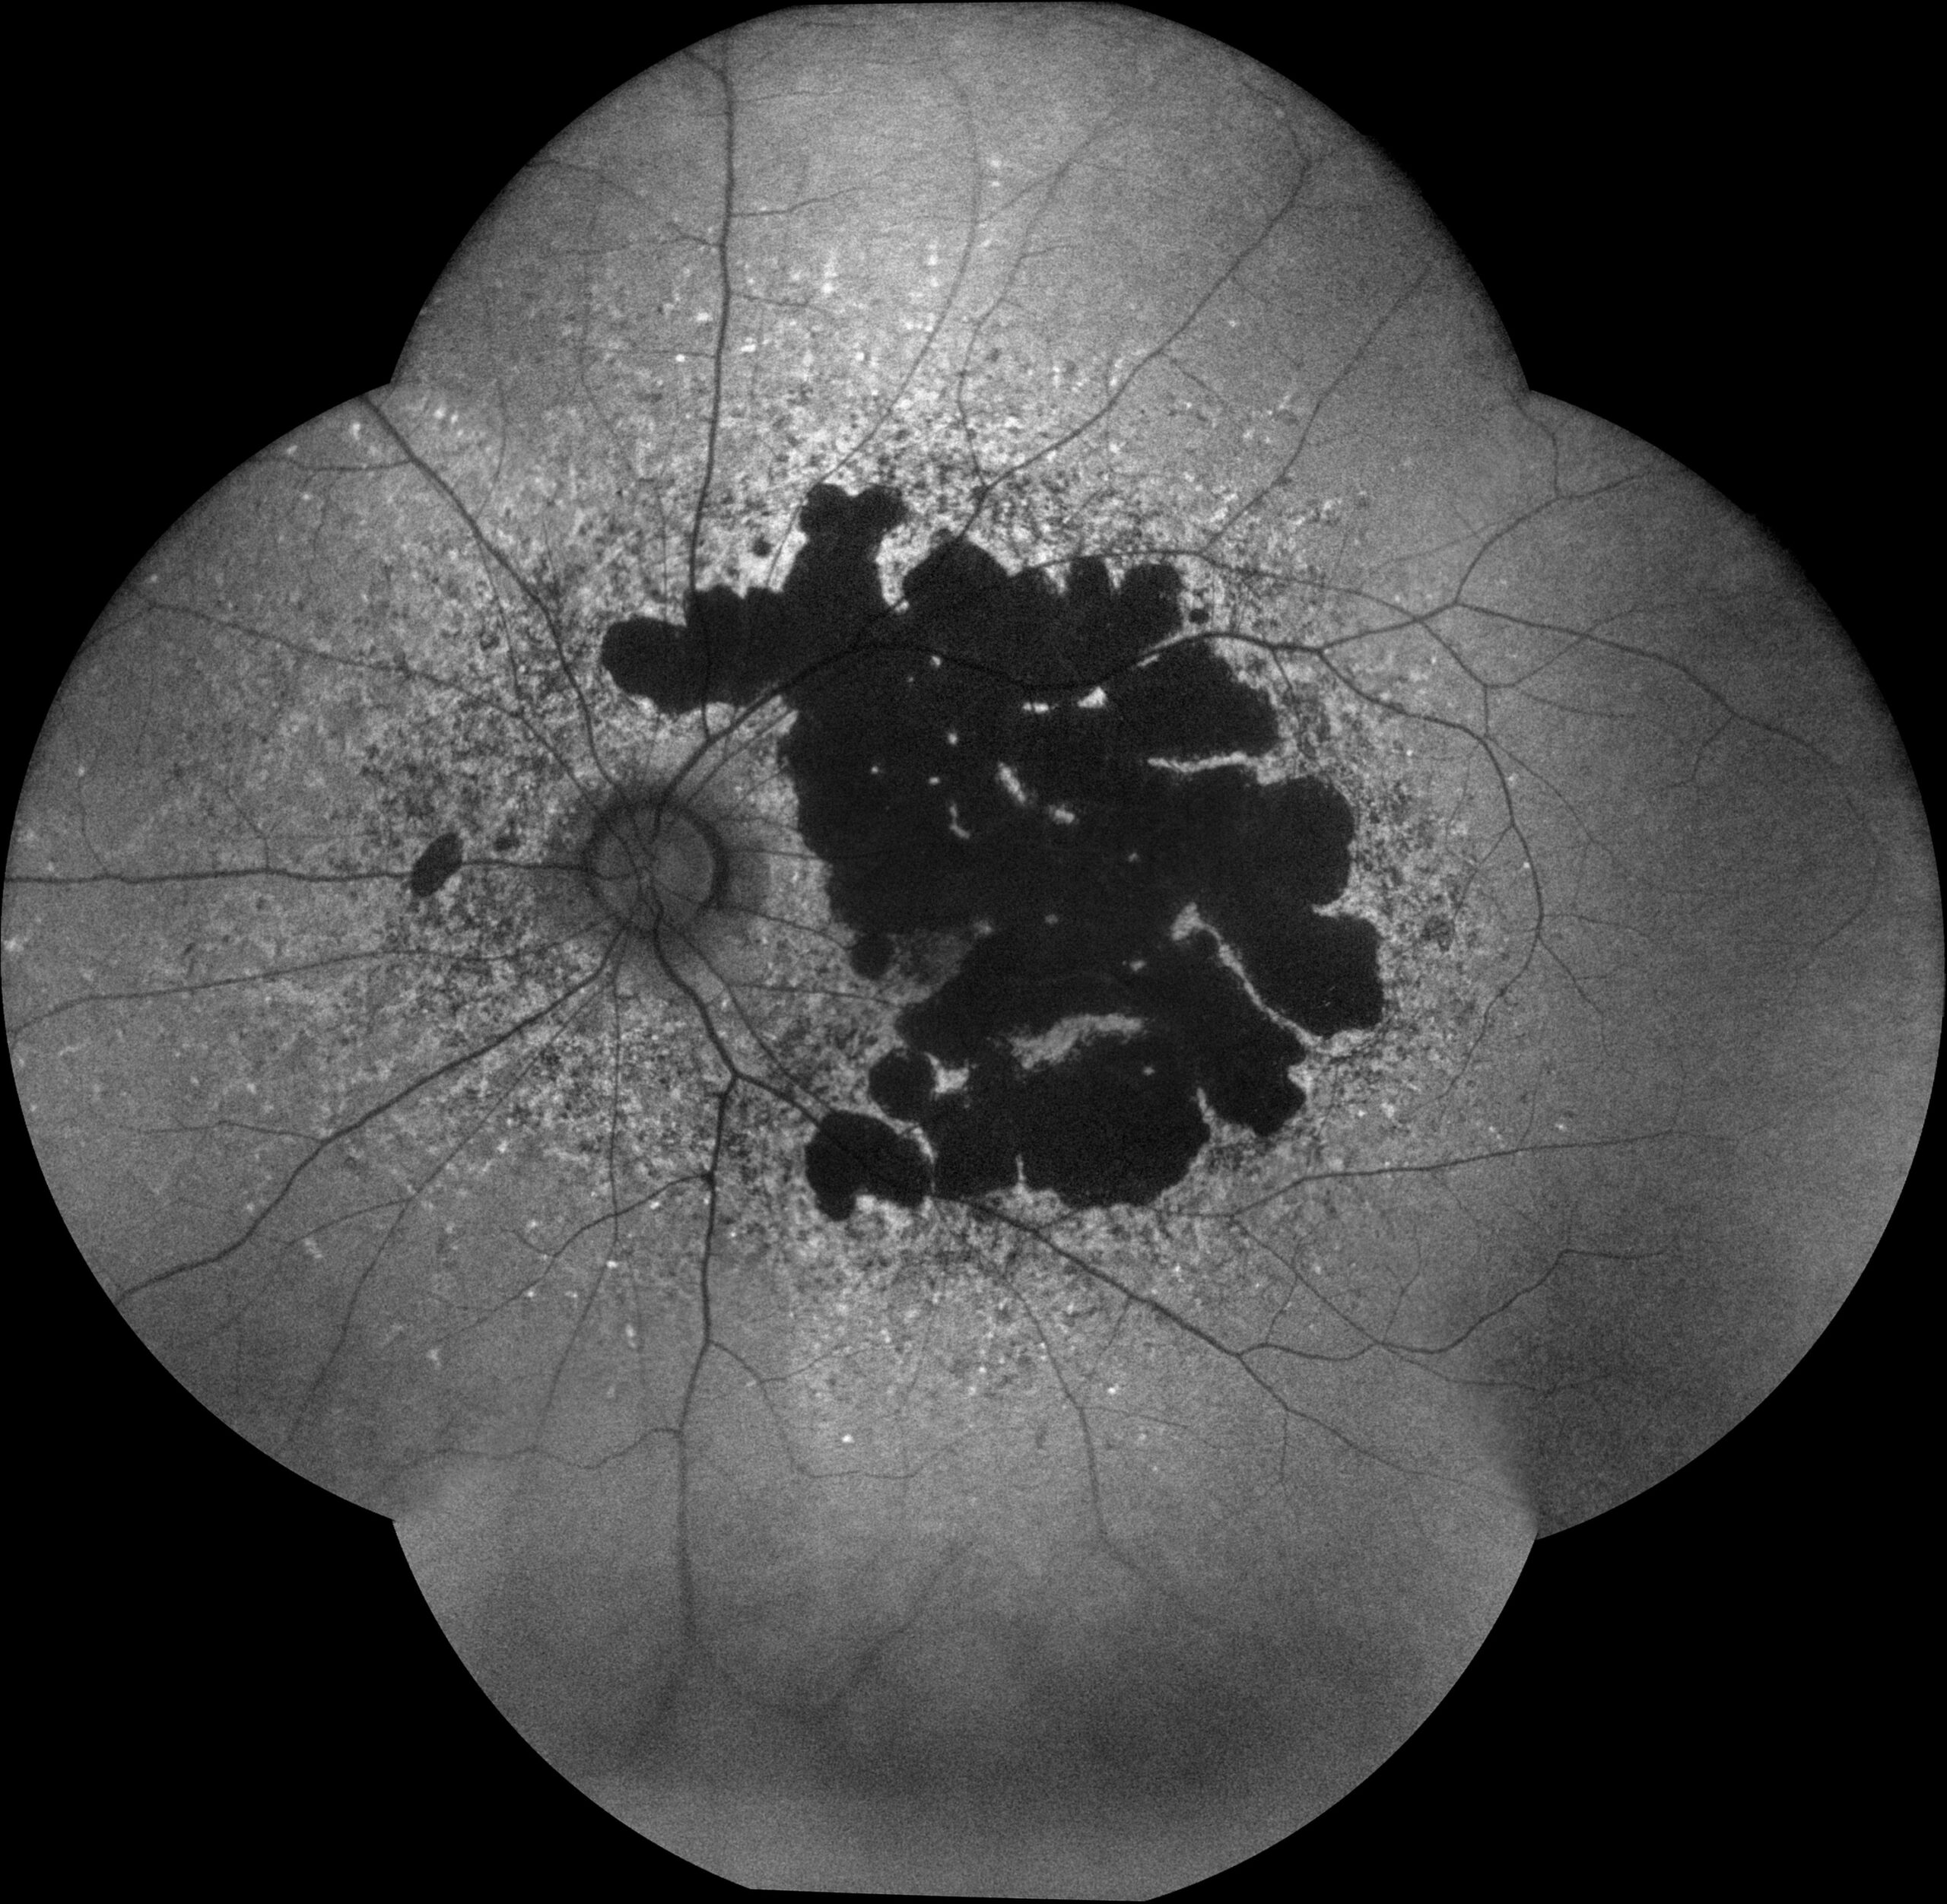

✓ Autofluorescence mode